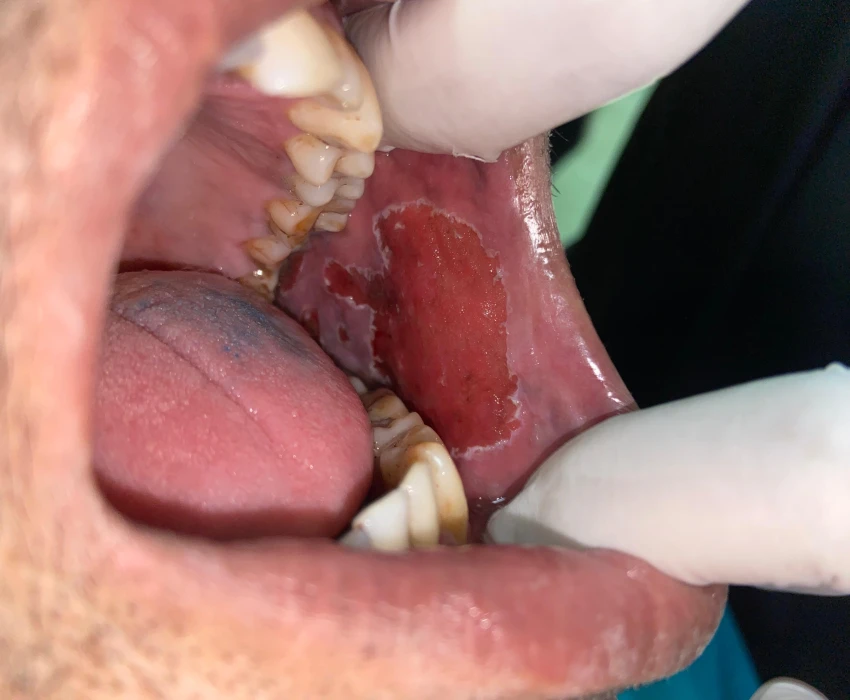

Exfoliative cytology was performed which came out as mild dysplasia.

Laser ablation of the lesion was done with the help of 940nm diode LASER (BIOLASE).